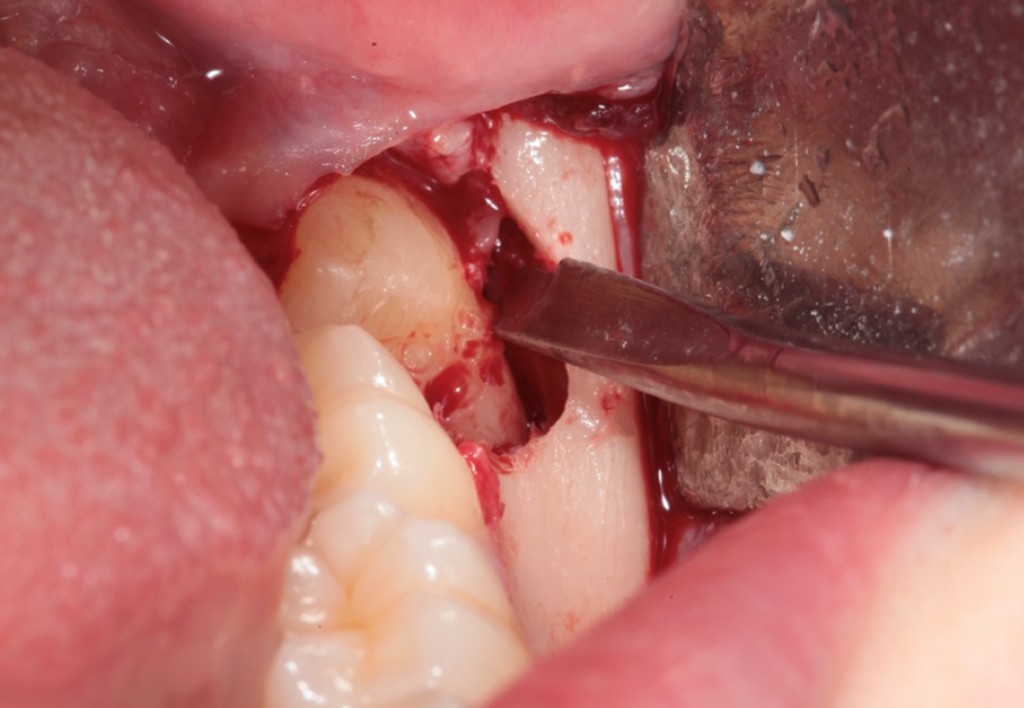

► Tecniche chirurgiche per elementi complessi

Approccio ad elementi inclusi, parzialmente inclusi, in arcata o sovrannumerari, con tecniche atraumatiche e sicure.

Galleria fotografica